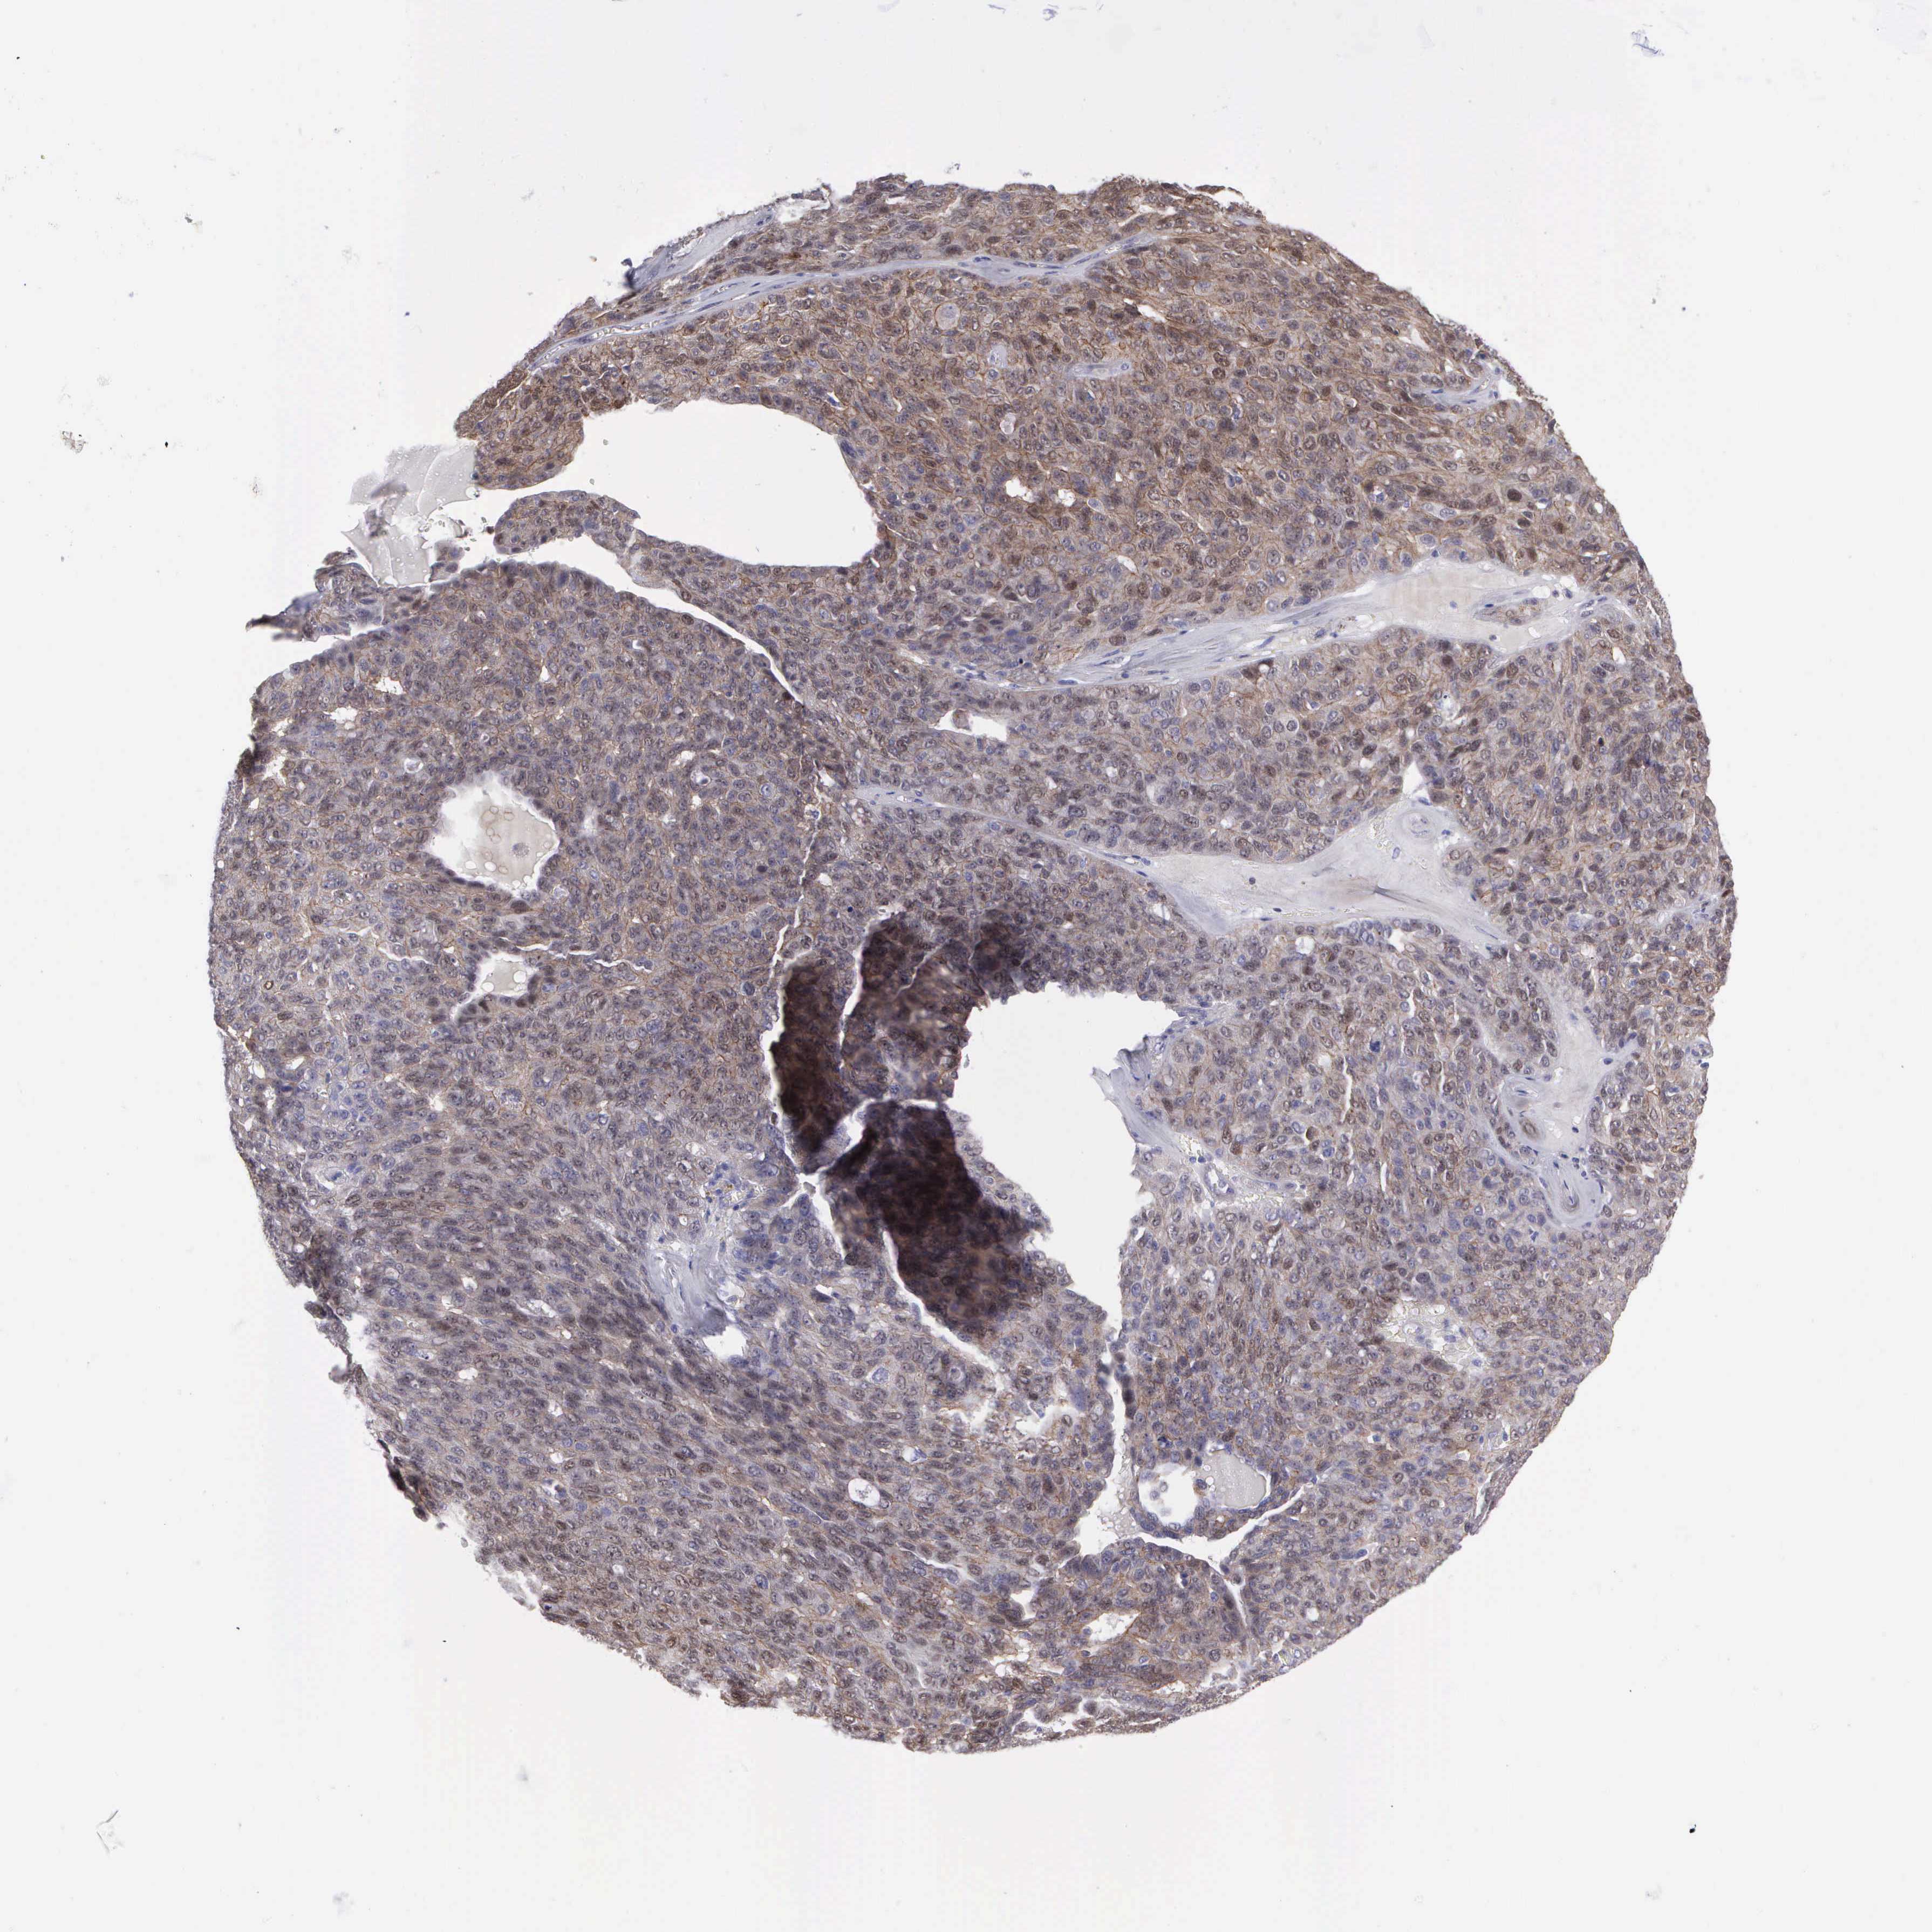

OVARIAN CANCER - Protein expressioni

A mouse-over function shows sample information and annotation data. Click on an image to view it in a full screen mode. Samples can be filtered based on level of antibody staining by selecting one or several of the following categories: high, medium, low and not detected. The assay and annotation is described here.

Note that samples used for immunohistochemistry by the Human Protein Atlas do not correspond to samples in the TCGA dataset.

Antibody stainingi

Antibody staining in the annotated cell types in the current human tissue is reported as not detected, low, medium, or high, based on conventional immunohistochemistry profiling in selected tissues. This score is based on the combination of the staining intensity and fraction of stained cells.

Each image is clickable and will lead to virtual microscopy that enables deeper exploration of all samples and also displays staining intensity scores, fraction scores and subcellular localization as well as patient and tissue information for each sample.

Antibody HPA000639

Staining

High

Medium

Low

Not detected

Intensity

Strong

Moderate

Weak

Negative

Quantity

>75%

75%-25%

<25%

None

Location

Nuclear

Cytoplasmic/membranous

Cytoplasmic/membranous,nuclear

Cystadenocarcinoma, mucinous, NOS

Carcinoma, endometroid

Cystadenocarcinoma, serous, NOS